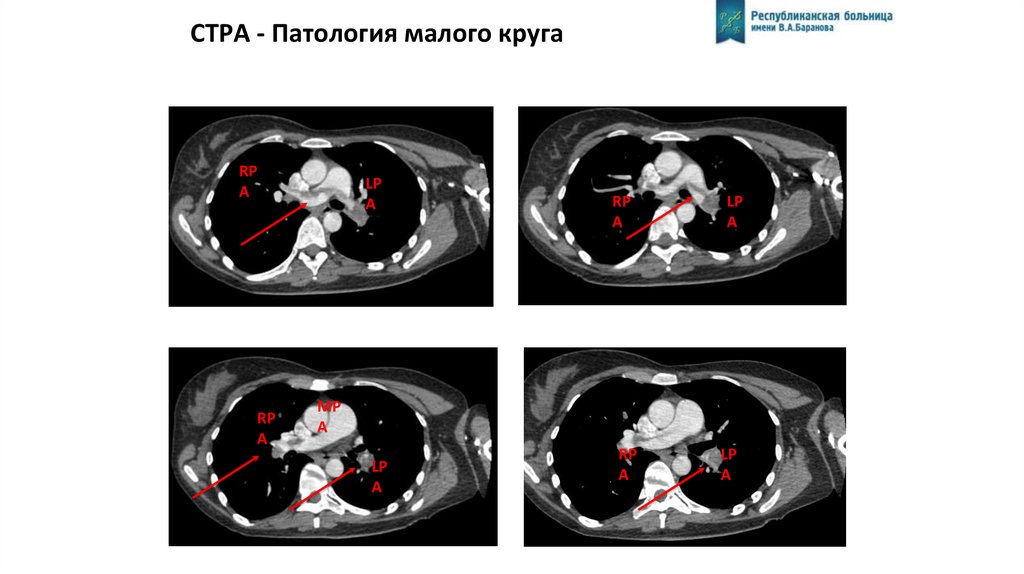

CTPA - Патология малого круга

RP

A

LP

MP